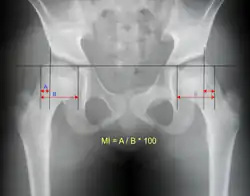

- Reimer's migration index (MI), also called the femoral extrusion index,[3] is calculated if hip dysplasia is detected. It can be used to indicate hip dislocation. It is the horizontal distance (parallel to the Hilgenreiner Line) between the Perkin line and the lateral border of the ossification center of the femoral head, divided by the horizontal width of the ossification center. The migration index is normally less than 33% by most sources,[9] but 25% and 30% has also been suggested.[10]